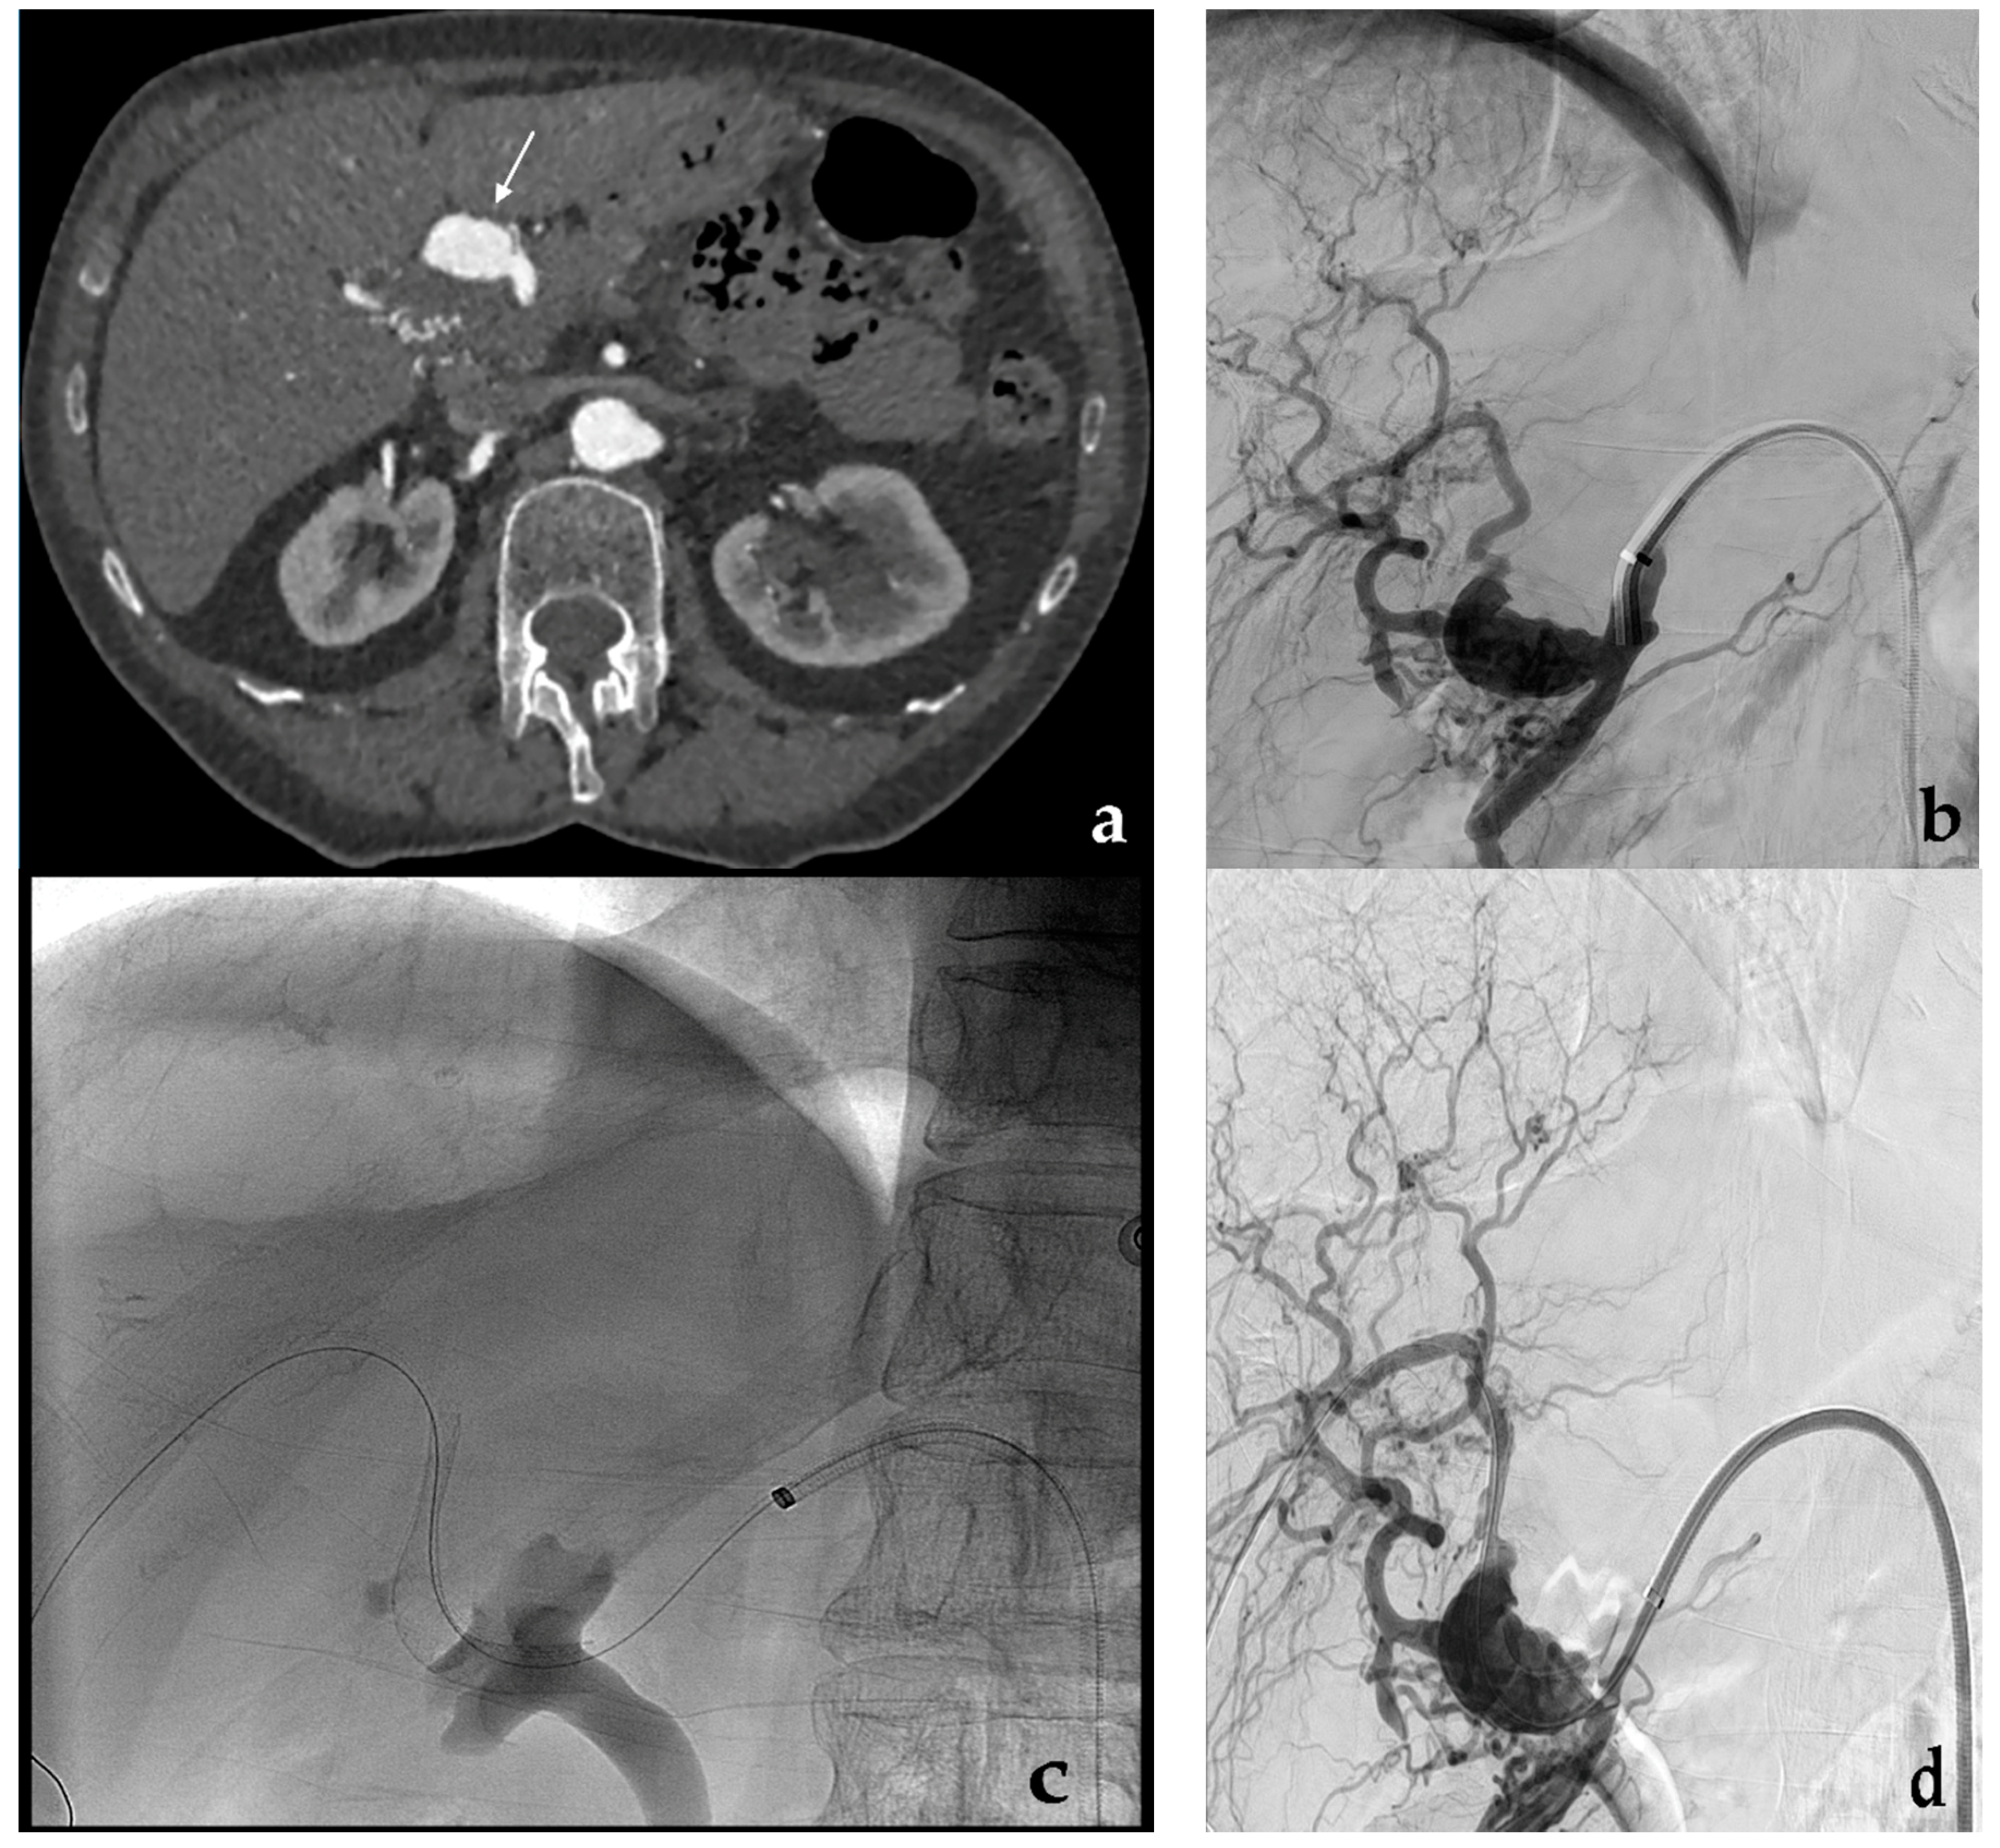

3.1. Coil Embolization

- Venturini, M.; Marra, P.; Colombo, M.; Alparone, M.; Agostini, G.; Bertoglio, L.; Sallemi, C.; Salvioni, M.; Gusmini, S.; Balzano, G.; et al. Endovascular treatment of visceral artery aneurysms and pseudoaneurysms in 100 Patients: Covered stenting vs transcatheter embolization. J. Endovasc. Ther. 2017, 24, 709–717. [Google Scholar] [CrossRef] [PubMed]

- Venturini, M.; Marra, P.; Colombo, M.; Panzeri, M.; Gusmini, S.; Sallemi, C.; Salvioni, M.; Lanza, C.; Agostini, G.; Balzano, G.; et al. Endovascular repair of 40 visceral artery aneurysms and pseudoaneurysms with the Viabahn Stent-Graft: Technical aspects, clinical outcome and mid-term patency. Cardiovasc. Interv. Radiol. 2018, 41, 385–397. [Google Scholar] [CrossRef]